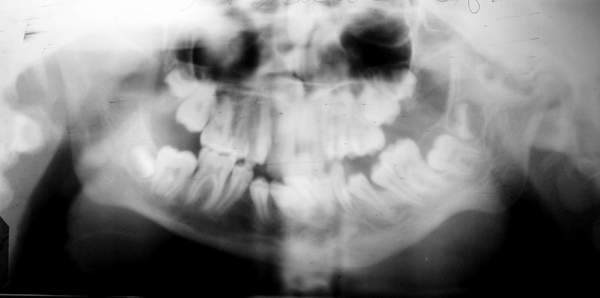

Пациент В., 13 лет. Диагноз: Костный анкилоз левого височно-нижнечелюстного сустава (ВНЧС), левосторонняя микрогения. Болеет с 2-х летнего возраста. Возможная причина развития анкилоза – воспалительный процесс (в первые 1,5 года жизни часто болел простудными заболеваниями, травму родители отрицают). В 3 и 5 лет проводилась редрессация – безуспешно.Прилагаются: ортопантомограмма, кадры СКТ с 3Д реконструкцией. Вопросы: определение тактики лечения – вид и сроки реконструктивно-пластической операции (этапов операции), а именно – неоартропластики и устранения микрогении, медикаментозная терапия в до- и послеоперационный период, ортодонтическое лечение.